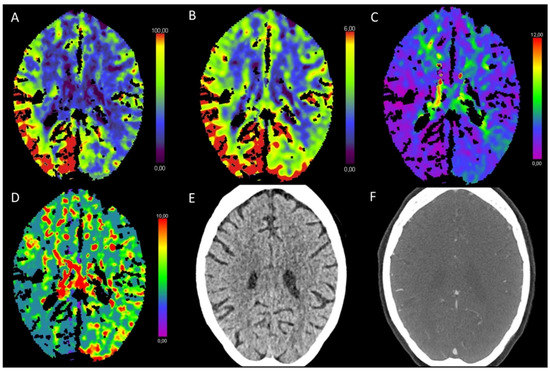

3.1. Acute Supratentorial Stroke

3.5. Hypotensive Cerebral Infarction (HCI) with Watershed Infarcts/Border Zones